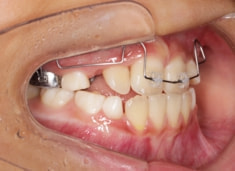

治療前

治療開始時